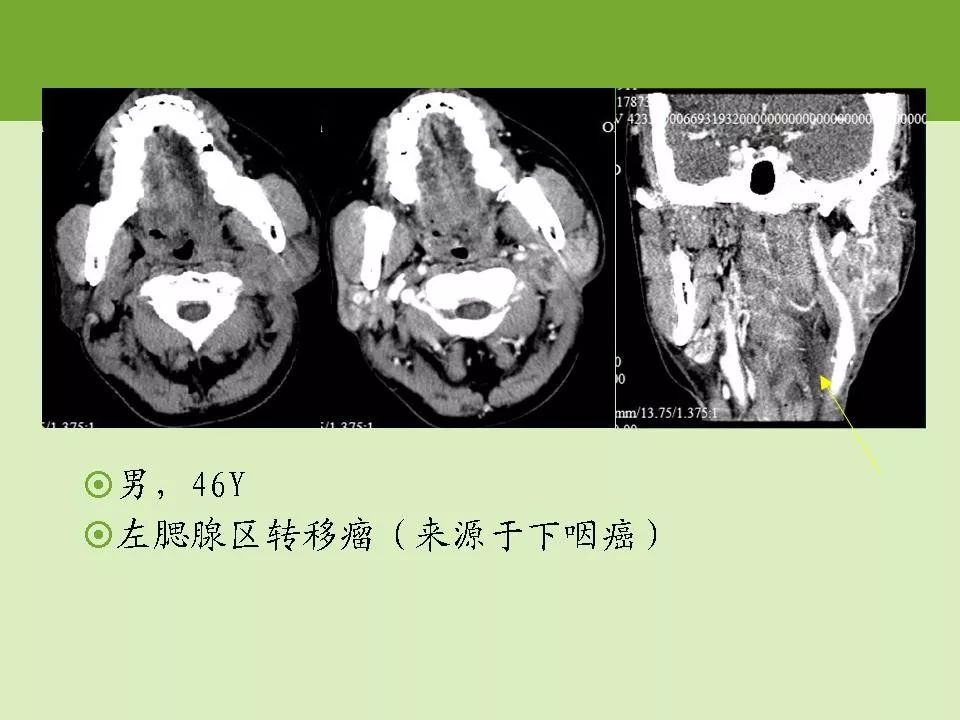

读片腮腺ct平扫病例

图片尺寸1025x857